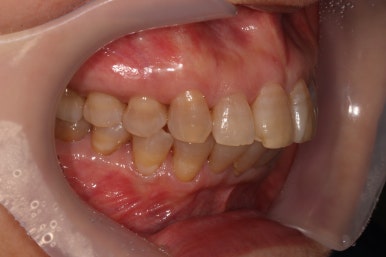

상당히 뻐드러져 있었던 앞니가 적절한 위치를 찾아가고 있는지 확인을 하기 위해 측면 사진도 찍어봅니다.

저희 치과에서는 Overjet이라고 표현하는데, 윗니가 아랫니를 약 1-2mm 정도 덮는 모양이어야 평균이라고 봅니다.

보시면 위와 아래 치아 사이에 약간의 틈이 있는 것을 보실 수 있죠? 점점 개선될거에요!!